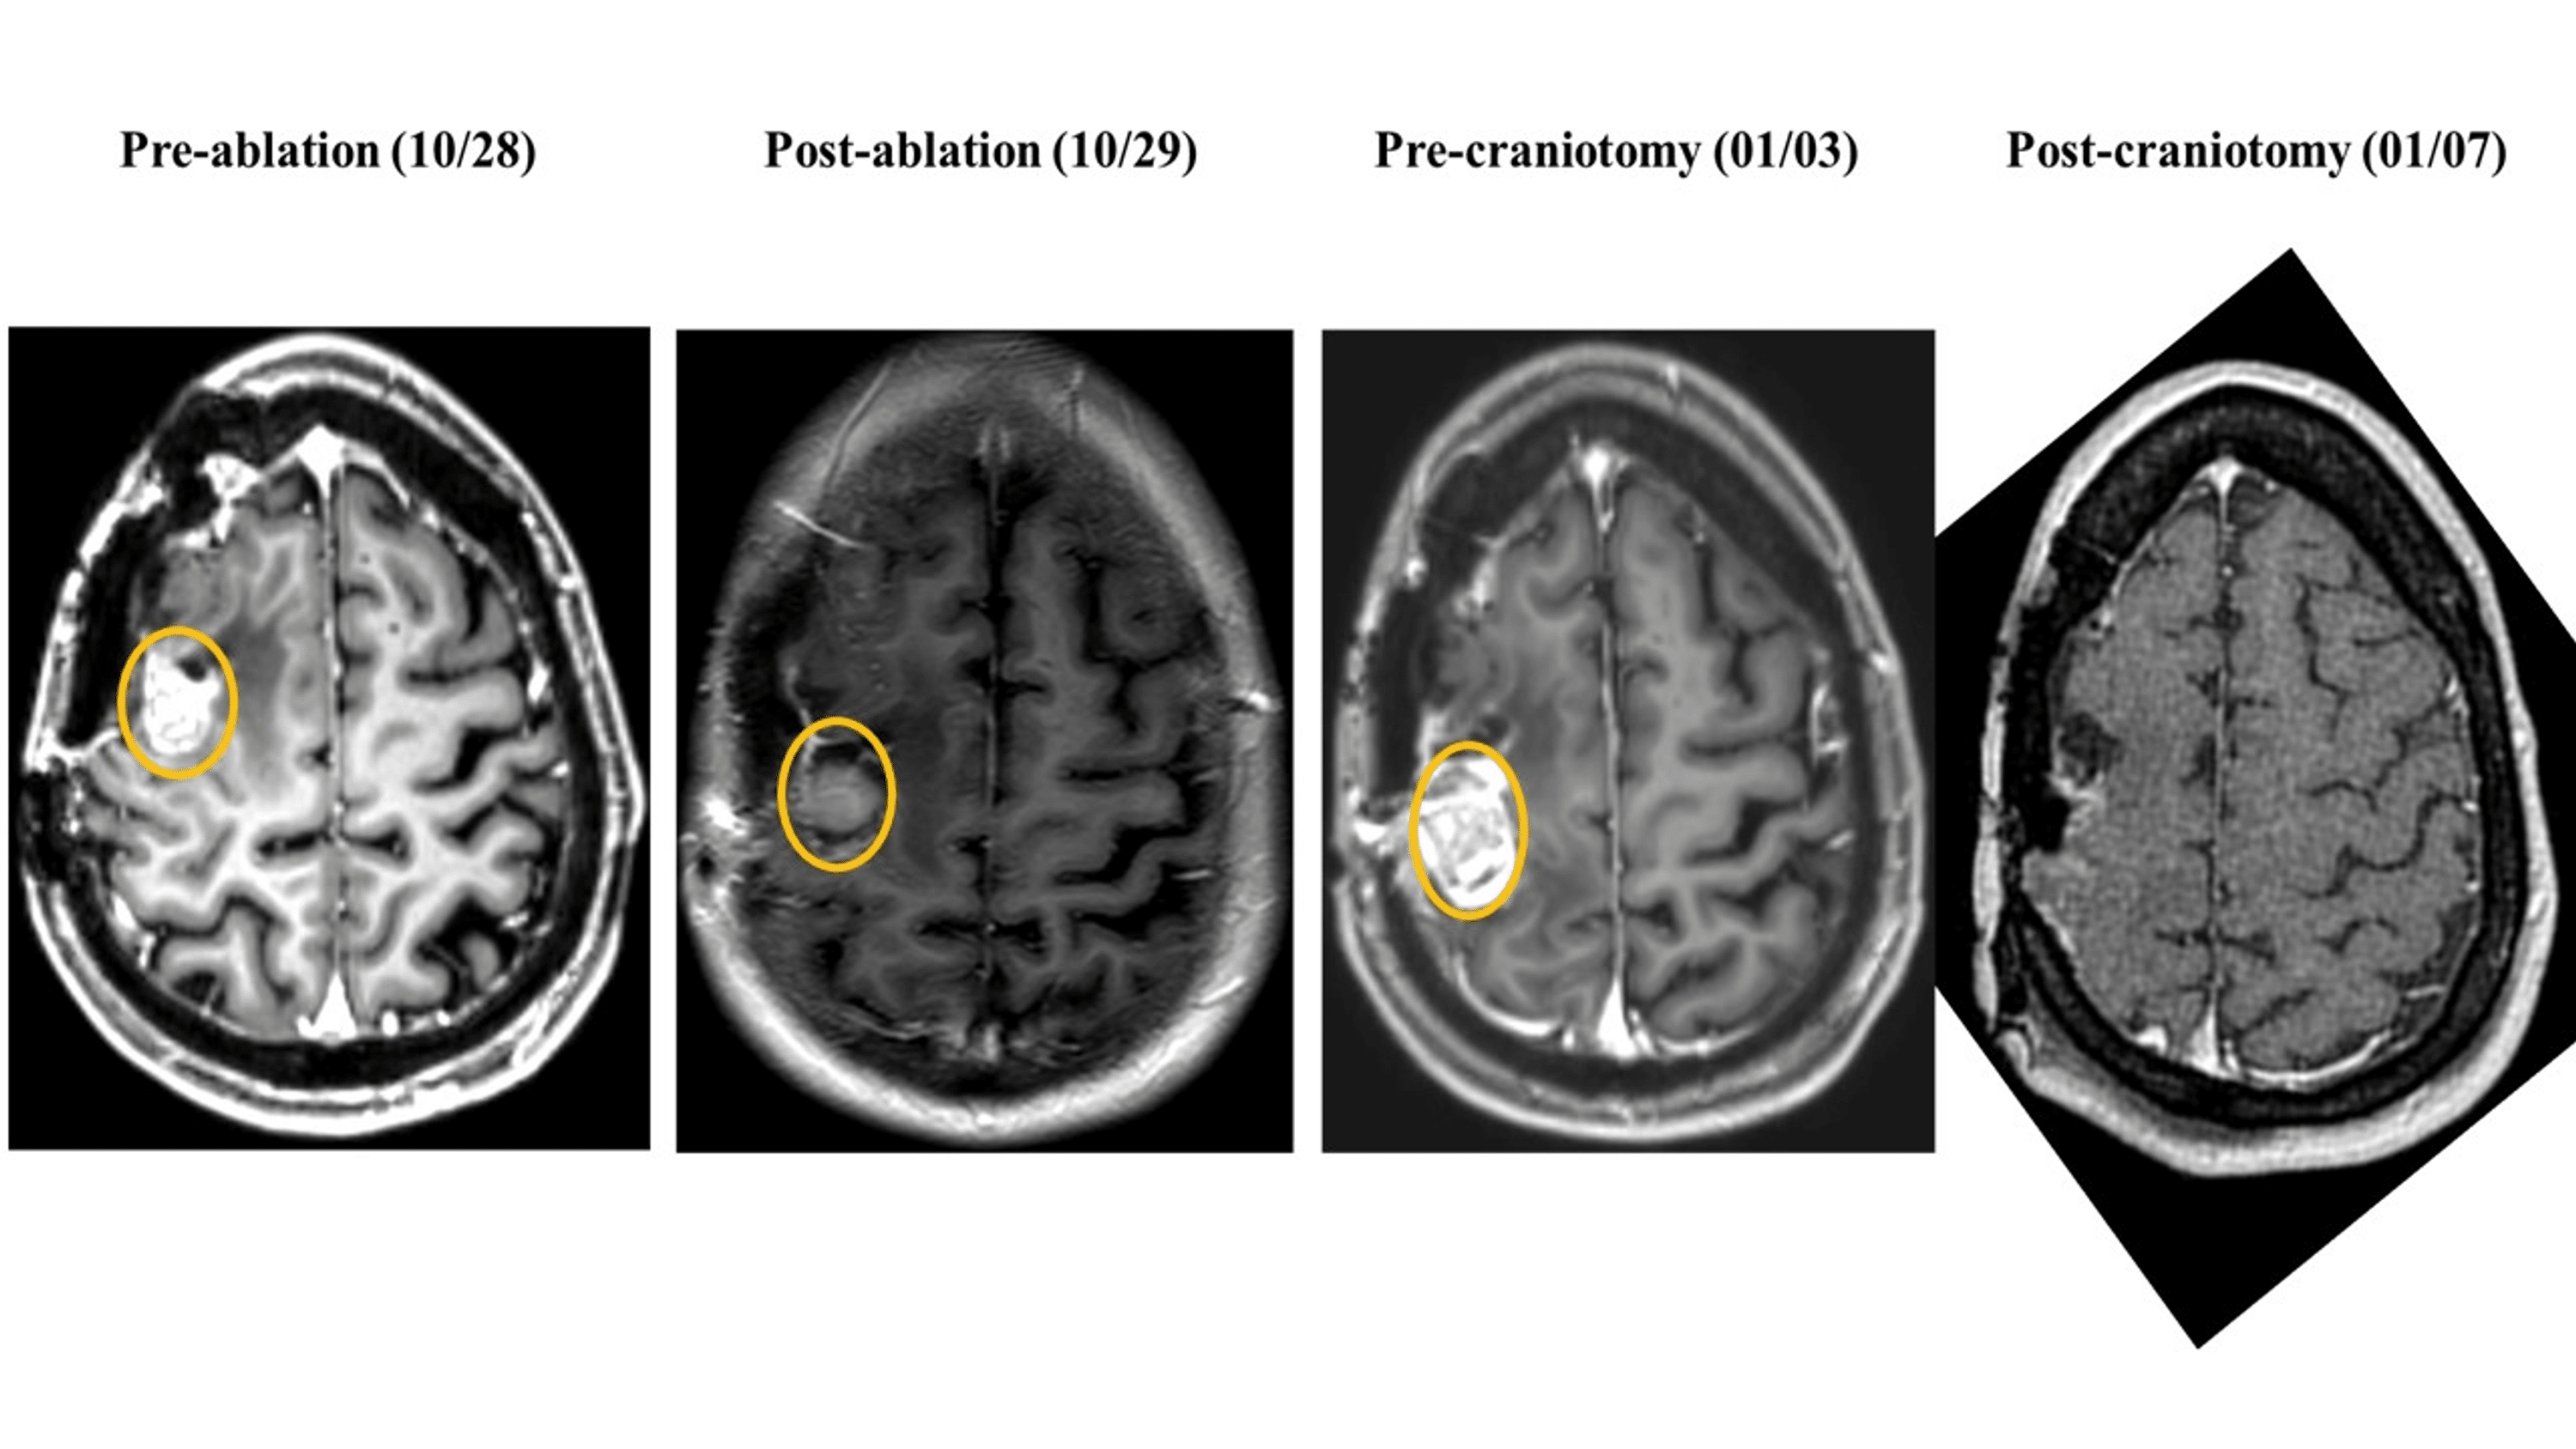

Case Presentation Minimally Invasive Laser Ablation Treatment for What Is Brain Abrasion Abrasions are superficial cuts or scrapes to skin that occur due to impact, pressure, or friction. Minor abrasions are typically treated at home. The brain contusions are lesions with a hemorrhagic character that begins in the brain cortical. It can come from trauma, such as a car accident, or from a medical. Focal brain injury affects only one region of. What Is Brain Abrasion.